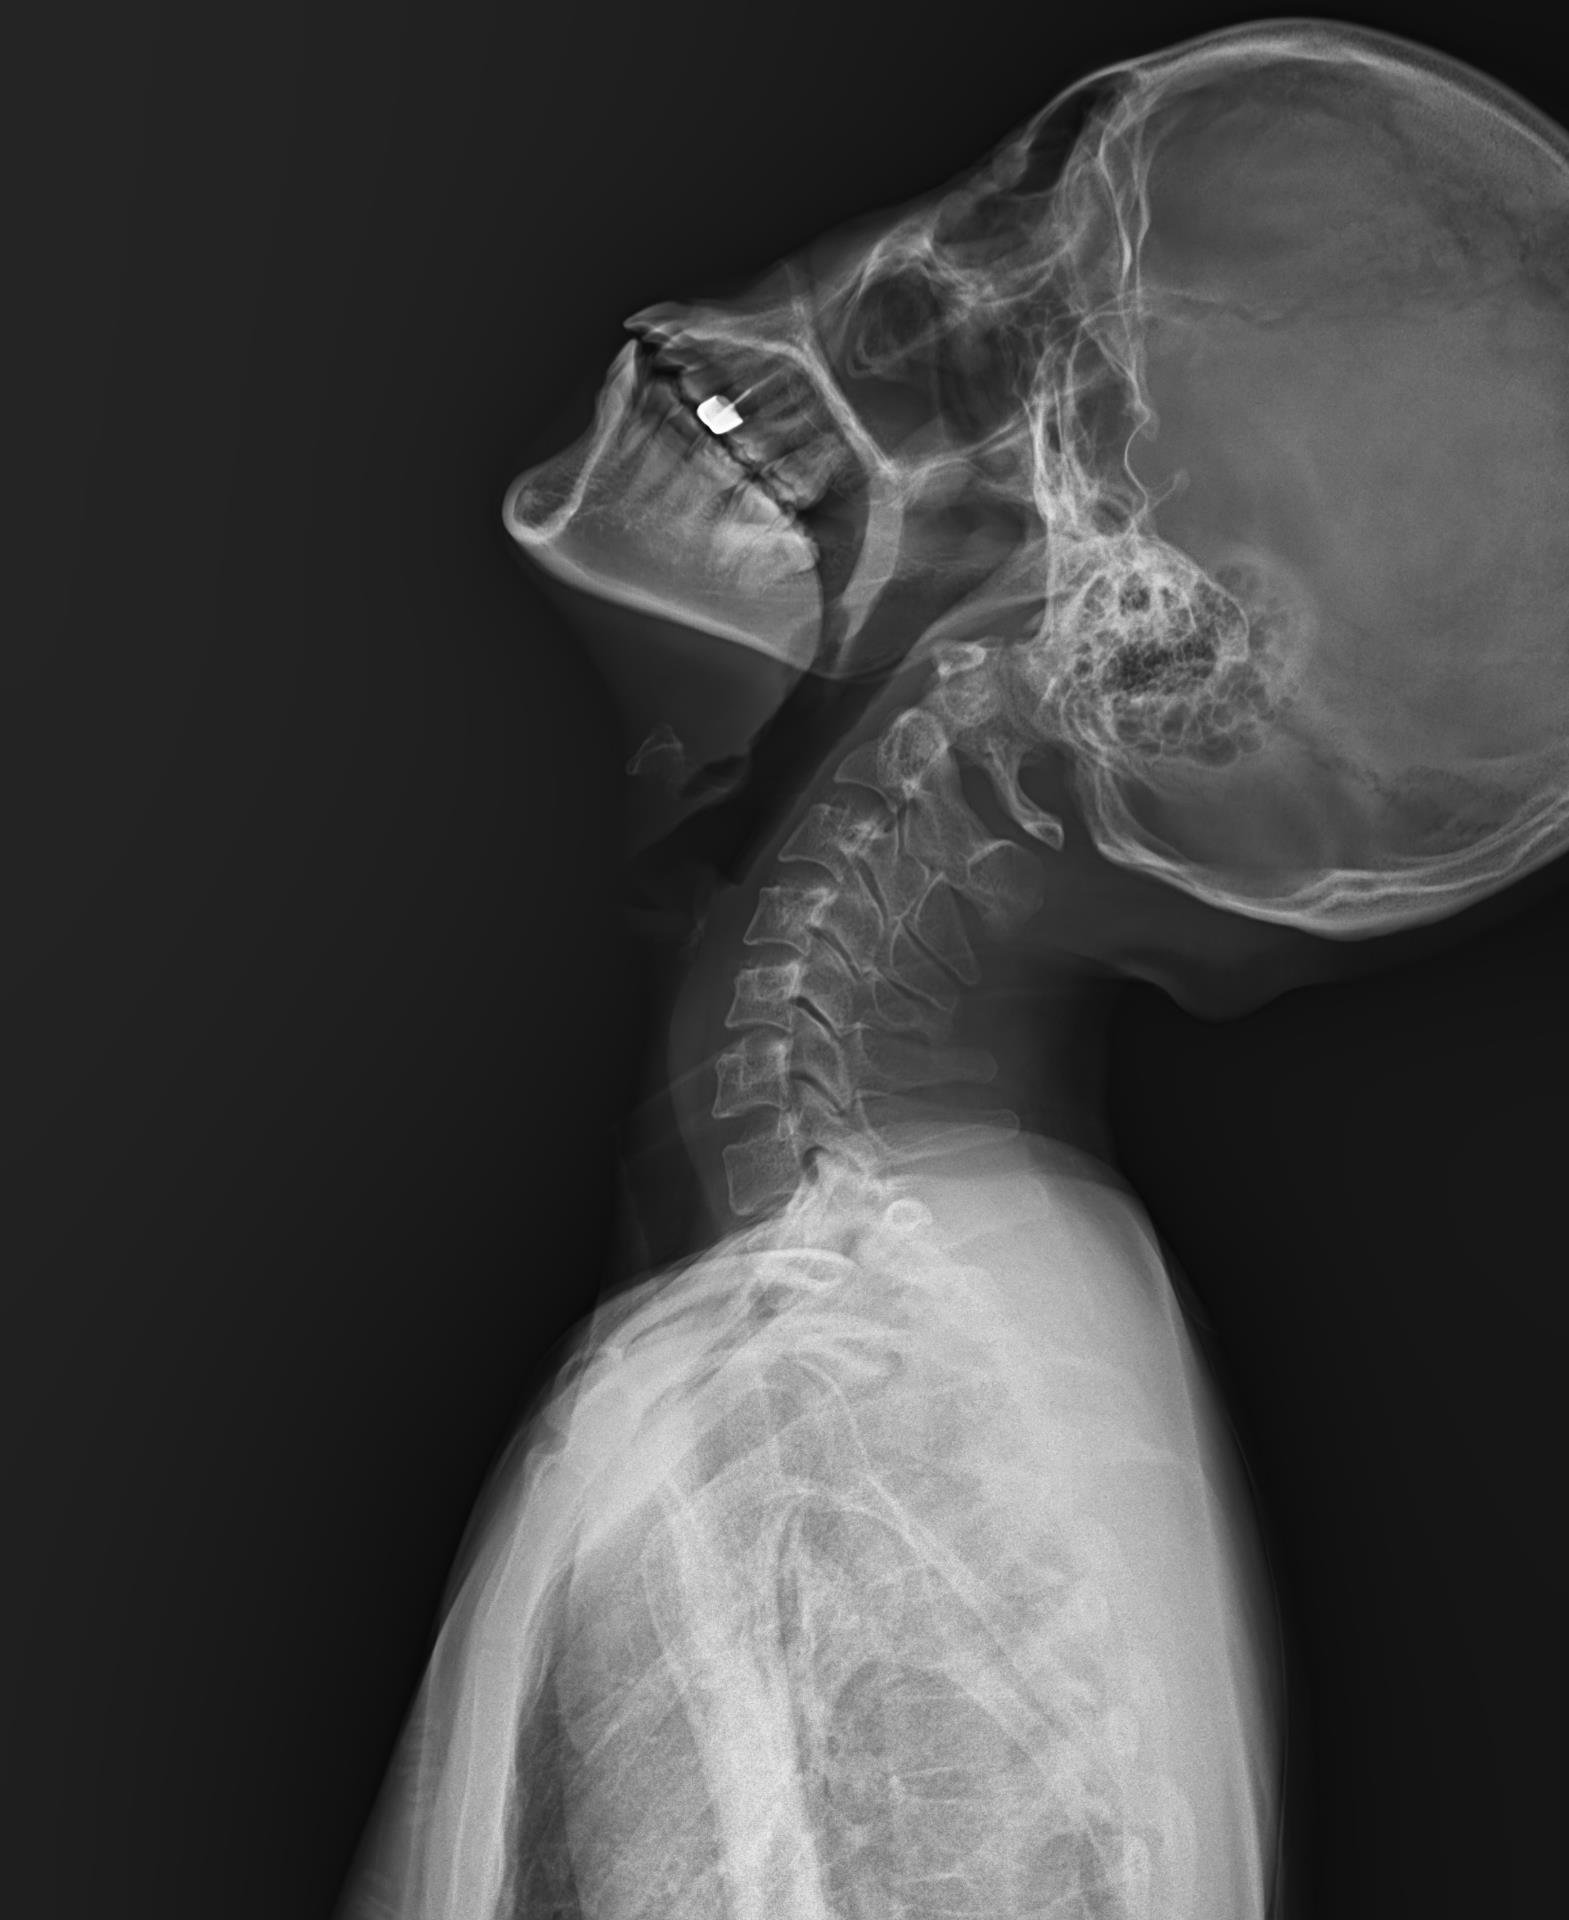

Ảnh chụp X-Quang cột sống (ảnh trên: một phần, ảnh dưới: toàn phần)

Chụp X-quang cột sống là kỹ thuật sử dụng tia X để ghi lại hình ảnh cấu trúc xương của cột sống, bao gồm các đốt sống cổ, ngực, thắt lưng và xương cùng. Với X-quang cột sống toàn phần, bác sĩ có thể quan sát cột sống như một chỉnh thể thống nhất, thay vì chỉ nhìn từng đoạn riêng lẻ.

Chụp X-quang toàn bộ cột sống là phương pháp chẩn đoán hình ảnh giúp bác sĩ đánh giá tổng thể cấu trúc xương sống, từ đó phát hiện sớm nhiều bất thường và bệnh lý quan trọng. Thay vì chỉ quan sát từng đoạn riêng lẻ, kỹ thuật này cho phép nhìn cột sống như một chỉnh thể thống nhất, phản ánh đúng trục chịu lực và sự liên kết giữa các vùng cổ – ngực – thắt lưng – xương cùng.

Hình ảnh X-quang toàn bộ cột sống được ghi nhận ở nhiều tư thế, nhiều góc độ, giúp bác sĩ: